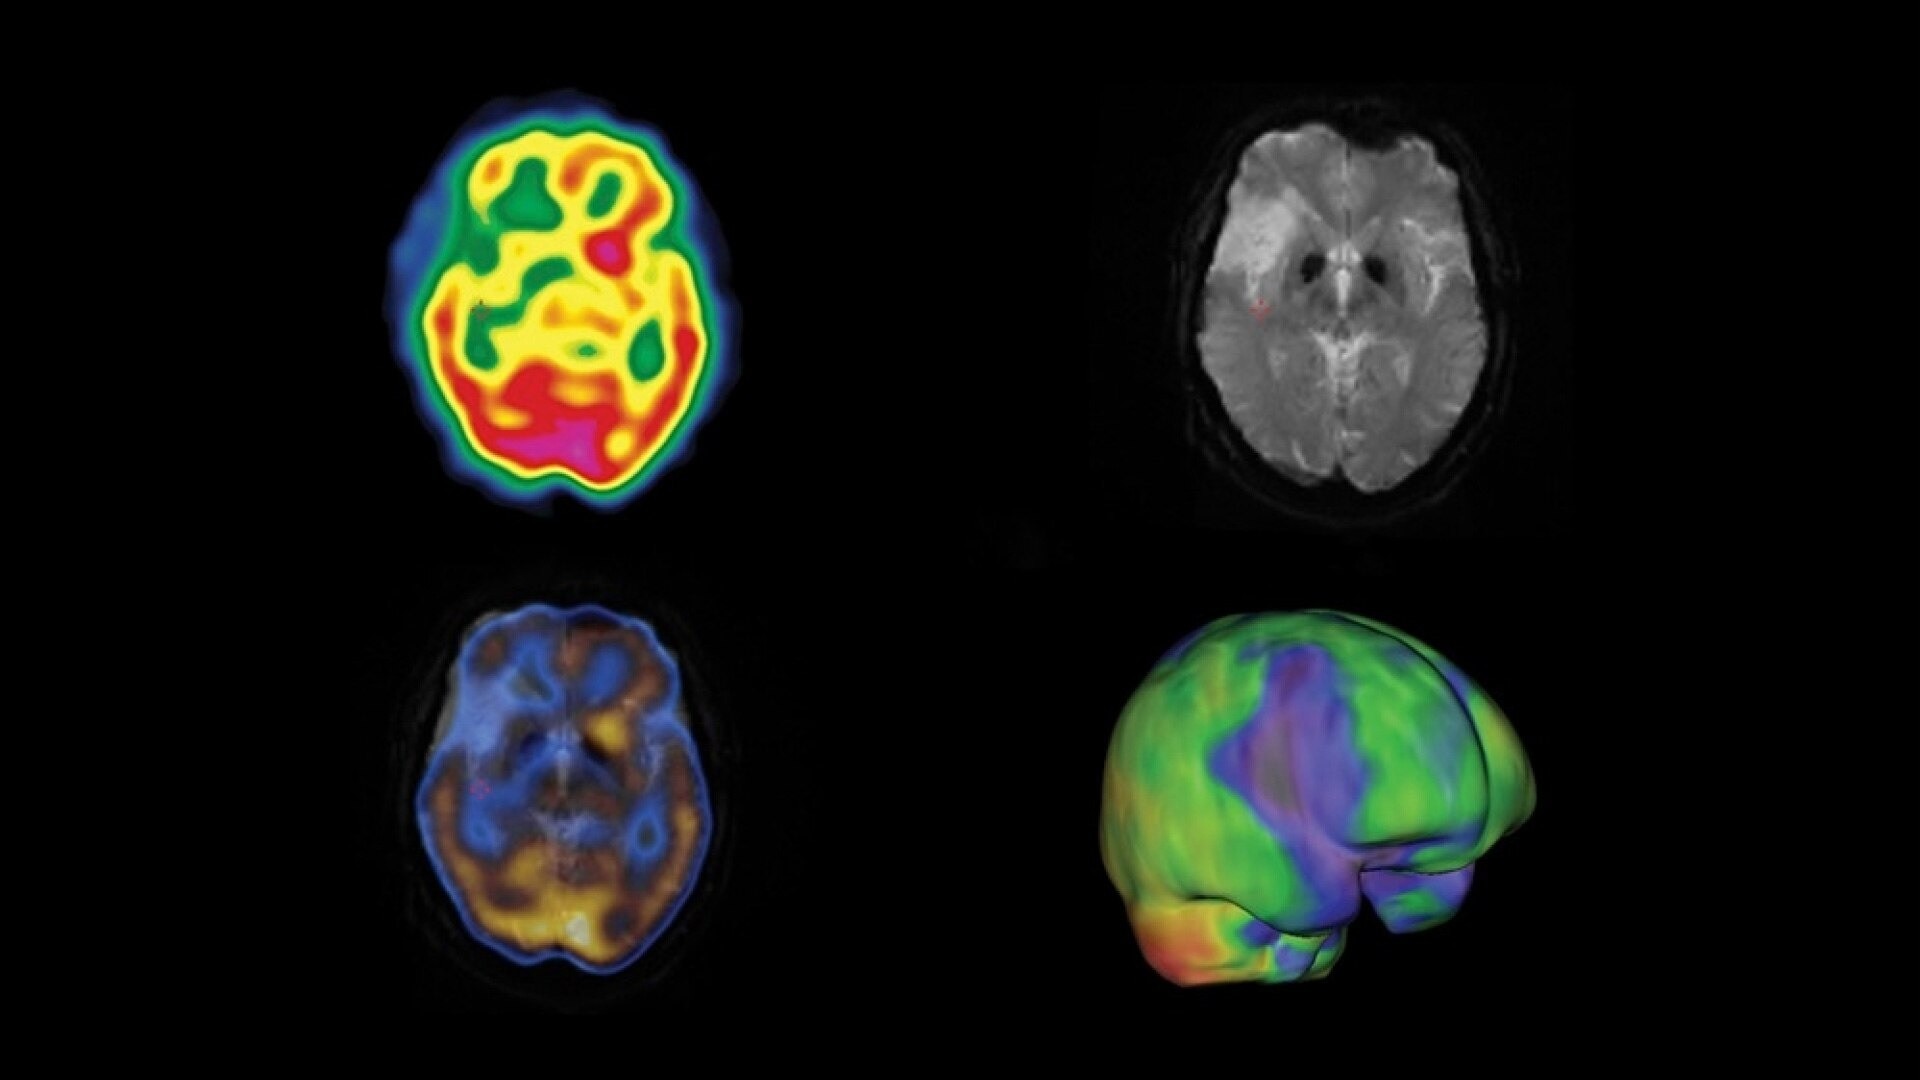

One home for all your molecular images

SmartConsole makes advanced procedures more accessible by transferring exams directly to the PACS or other pre-defined DICOM destinations with no operator intervention, even if SPECT/CT fusion is not supported, by exporting the studies in DICOM PET format. You can generate and send an additional dataset in PET DICOM format to enable quantitative SPECT results and SPECT SUV (Standard Uptake Value) on any PET DICOM compliant workstation or PACS. Referring physicians can review and evaluate your SPECT/CT exams with the same quality of information they have come to expect from your PET/CT, as adjunct information to the original SPECT/CT images.